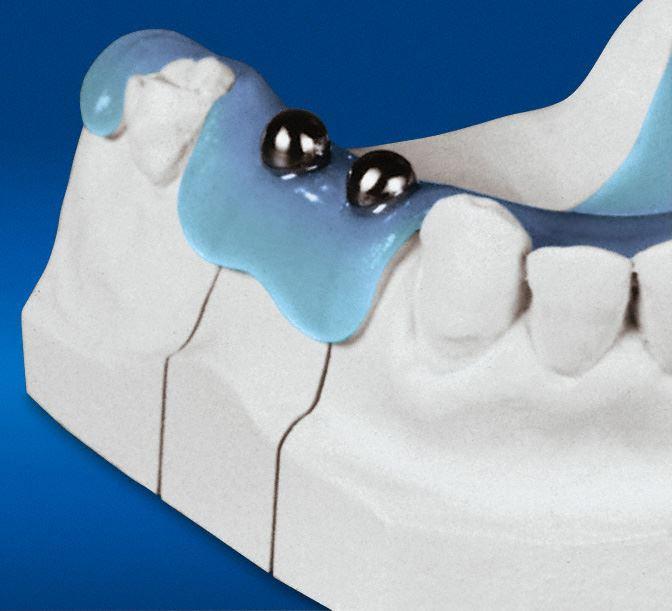

Mit einer Messkugelschablone können das vertikale Knochenangebot und die mögliche Implantatlänge festgestellt werden.

Die reale Knochenhöhe wird mit Hilfe einer Tiefziehschiene mit eingearbeiteten Metallkugeln ermittelt. Bei digitalen Röntgengeräten kann gegebenenfalls auf die Messaufnahmen verzichtet werden, da sie über ein integriertes Messtool verfügen. Zur Detailabklärung kann es erforderlich sein, zusätzliche Aufnahmen von einzelnen Zahnabschnitten zu machen.